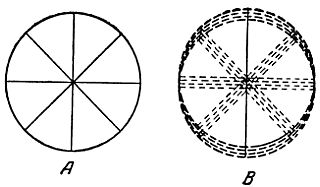

Для испытания глаз на астигматизм врачи-окулисты часто применяют специальную таблицу (рис. 10), где двенадцать кружков имеют штриховку равной толщины через одинаковые интервалы.

Рис. 10. Фигура для определения степени и меры астигматизма глаза.

Глаз, обладающий астигматизмом, увидит линии одного или нескольких кружков более черными. Направление этих более черных линий позволяет сделать вывод о характере астигматизма глаза.